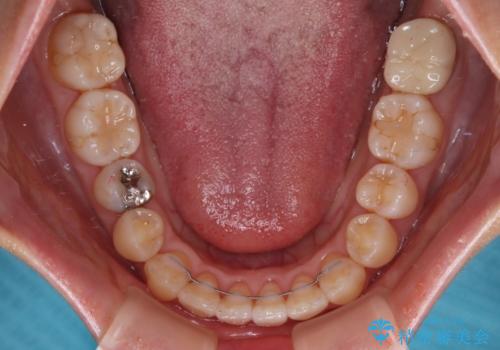

舌のトレーニングをしっかりと行っていただき、補綴治療も含めて1年強の短期間で治療を終えることができました。